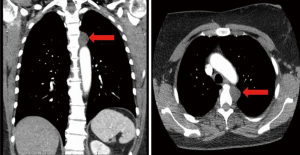

A 51-year-old Caucasian female presented for evaluation of a superior posterior mediastinal mass. The lesion was incidentally found after the patient was involved in a motor vehicle collision. During her trauma evaluation, a computed tomography scan of the chest showed a left paraspinal lesion measuring 2.4 cm by 2 cm (Figure 1). The Hounsfield units were consistent with fluid versus low density soft tissue mass.